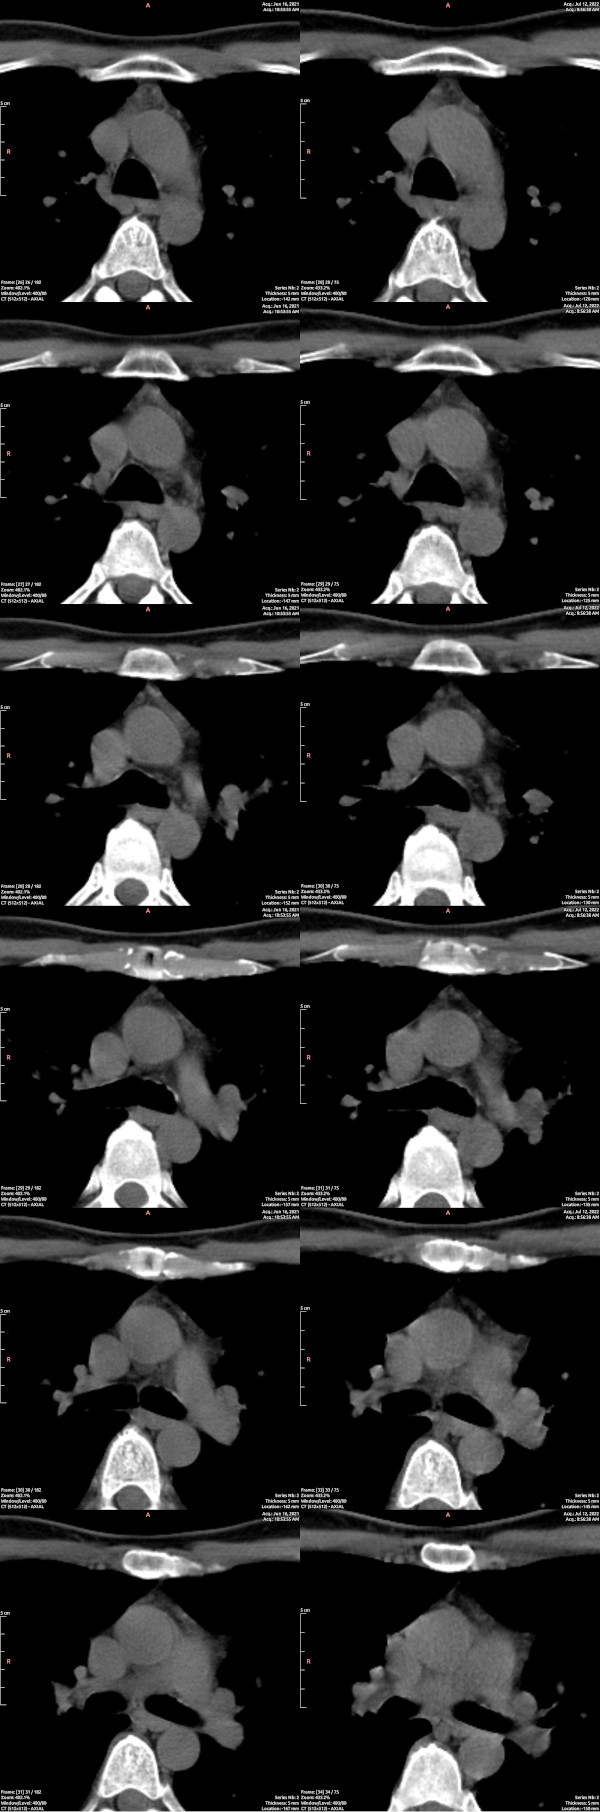

CT images of the thymus showed a visible reduction in active tissue across the nine months of the study, the opposite of the hoped outcome. In the image below, paired cross-sections through the chest are shown, before on the left, after on the right. For guidance on reading CT scans of the thymus, refer to “Normal Thymus in Adults: Appearance on CT and Associations with Age, Sex, BMI and Smoking“. In a cross-section of the chest, as below, and as in the examples given in that paper, the thymus is the triangular patchy grey structure closer to the top of the image, immediately below the sternum (white). Areas of fat will appear dark in the range chosen here, and thus a more atrophied thymus, in which more active tissue is replaced with fat, will appear darker. By late life, the thymus is entirely dark, fatty.